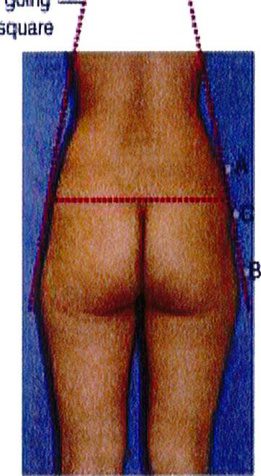

Việc phân loại các loại khung được thực hiện bằng cách so sánh và đối chiếu lượng chất béo có sẵn trong 3 vùng cụ thể. Điểm nhô ra nhất ở vùng hông, giới hạn trên được đánh dấu là điểm A, điểm nhô ra nhiều nhất ở vùng đùi ngoài

là điểm B và điểm giữa mặt ngoài mông là điểm C (Hình 4).

Sự kết nối các điểm A và B ở mỗi bên của cơ thế dẫn tới việc xác định 4 loại khung cơ bản: Hình chữ A, hình chữ V, hình vuông và hình tròn (Hình 5).